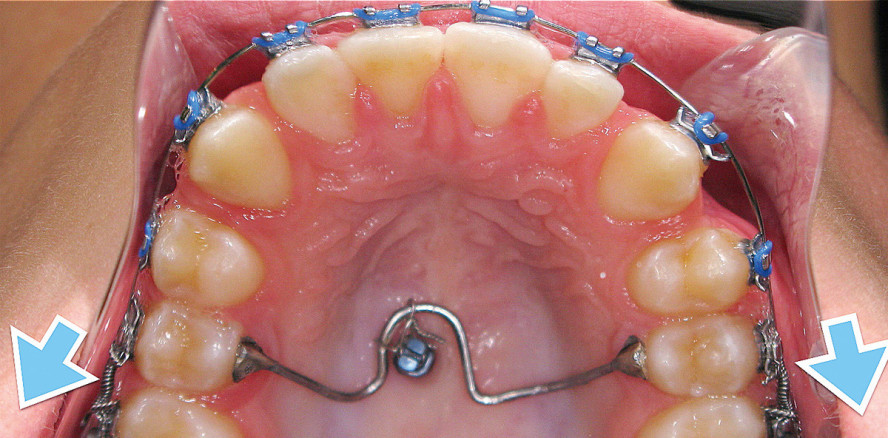

1. Biomechanische Probleme mit einem Transpalatinalbogen

Ein Transpalatinalbogen (Transpalatal Arch, TPA), eingesetzt in Kombination mit skelettaler  Verankerung, stellt eine der gängigsten Methoden zur Erzielung einer maximalen Verankerung im Oberkiefer dar. Abbildung 1 zeigt ein klinisches Beispiel, bei dem zwei Minischrauben im Bereich des mittleren Gaumens platziert wurden. Die zwei Schlaufen des TPA wurden mithilfe von Stahlligaturen mit den Pins verbunden. Zudem erfolgte das Kleben zweier Buttons (Knöpfchen) auf die Lingualflächen der oberen Eckzähne. Um die Rotation der Eckzähne zu vermeiden, während diese retrahiert wurden, wurden sowohl bukkale als auch linguale Retraktionskräfte appliziert. Ein weiteres Beispiel ist in den Abbildungen 2 und 3 zu sehen. Nach Insertion einer Minischraube im mittleren Gaumenbereich wurde auf den oberen zweiten Prämolaren ein Transpalatinalbogen geklebt und mittels Stahlligatur mit dem inserierten Pin verbunden. Zudem erfolgte die Platzierung offener Spiralfedern zwischen den oberen zweiten Prämolaren und ersten Molaren, um die oberen ersten Molaren zu distalisieren (Abb. 2). Zwar konnten die Lücken zwischen den ersten Molaren und zweiten Molaren im OK geöffnet werden, jedoch als sich die oberen ersten Molaren nach distal bewegten, bewegten sich die zweiten Prämolaren nach mesial (Abb. 3).